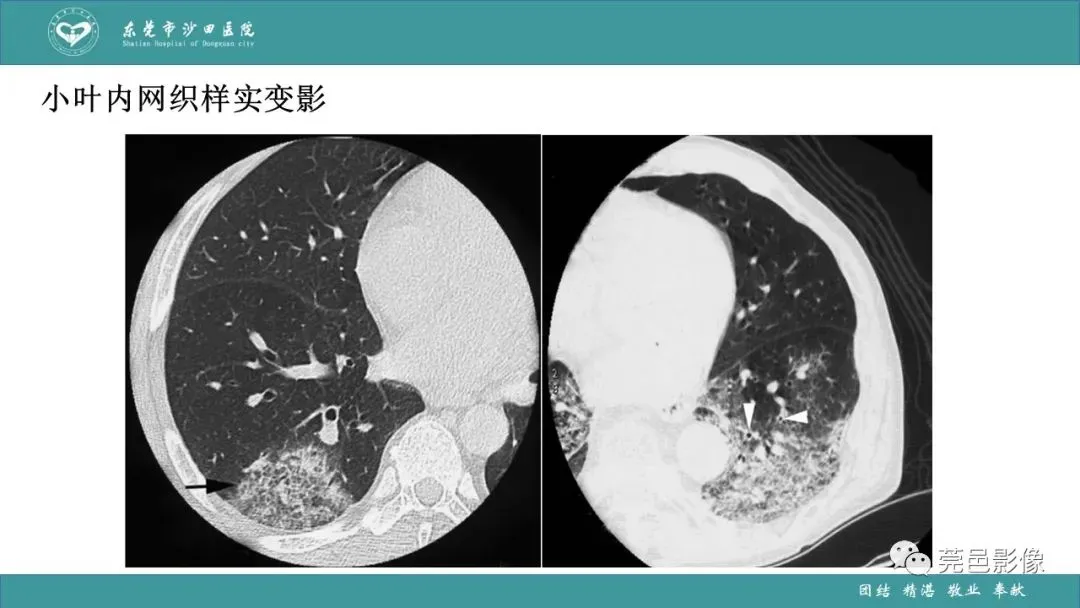

>课件 | 肺炎克雷伯杆菌肺炎影像学诊断与鉴别诊断

课件 | 肺炎克雷伯杆菌肺炎影像学诊断与鉴别诊断